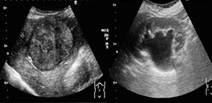

¢£ Ͳ»Çȸ¡ºº

Ͳ»Çȸ¡ºº¤Ï¡¢Êü¼ÍÀþ¤òÍøÍѤ·¤Æ¤¤¤Ê¤¤¤¿¤áÈï¤Ð¤¯¤¬¤Ê¤¯¡¢ÆýÍÄ»ù¤«¤é¤´¹âÎð¤ÎÊý¤Þ¤Ç°Â¿´¤·¤Æ¸¡ºº¤ò¼õ¤±¤Æ¤¤¤¿¤À¤±¤Þ¤¹¡£Åö¸¡ºº¼¼¤Ç¤Ï¡¢Aplio i800¡ÊCanon¼ÒÀ½¡Ë¡¢LOGIQ E10¡ÊGE¼ÒÀ½¡Ë¤ÎÁõÃÖ¤òƳÆþ¤·¤Æ¤¤¤Þ¤¹¡£Ê¢ÉôÁ´ÈÌ¡¢ÆýÁ£¡¦¹Ã¾õÁ£¤ò´Þ¤àÂÎɽ¡´ï¡¢ðôư̮¡¦»Í»è·ì´É¡Ê¿´Â¡¤ò½ü¤¯¡Ë¤Ê¤ÉÉý¹¤¤Îΰè¤Î¸¡ºº¤ò¹Ô¤Ã¤Æ¤¤¤Þ¤¹¡£¤Þ¤¿¡¢´Î¡¤Î¥¨¥é¥¹¥È¥°¥é¥Õ¥£¡Ê´Î¹ÅÅÙ¬Äê´Þ¤à¡Ë¡¢Â¤±ÆÄ¶²»Çȸ¡ºº¤Ë¤âÂбþ¤·¤Æ¤¤¤Þ¤¹¡£